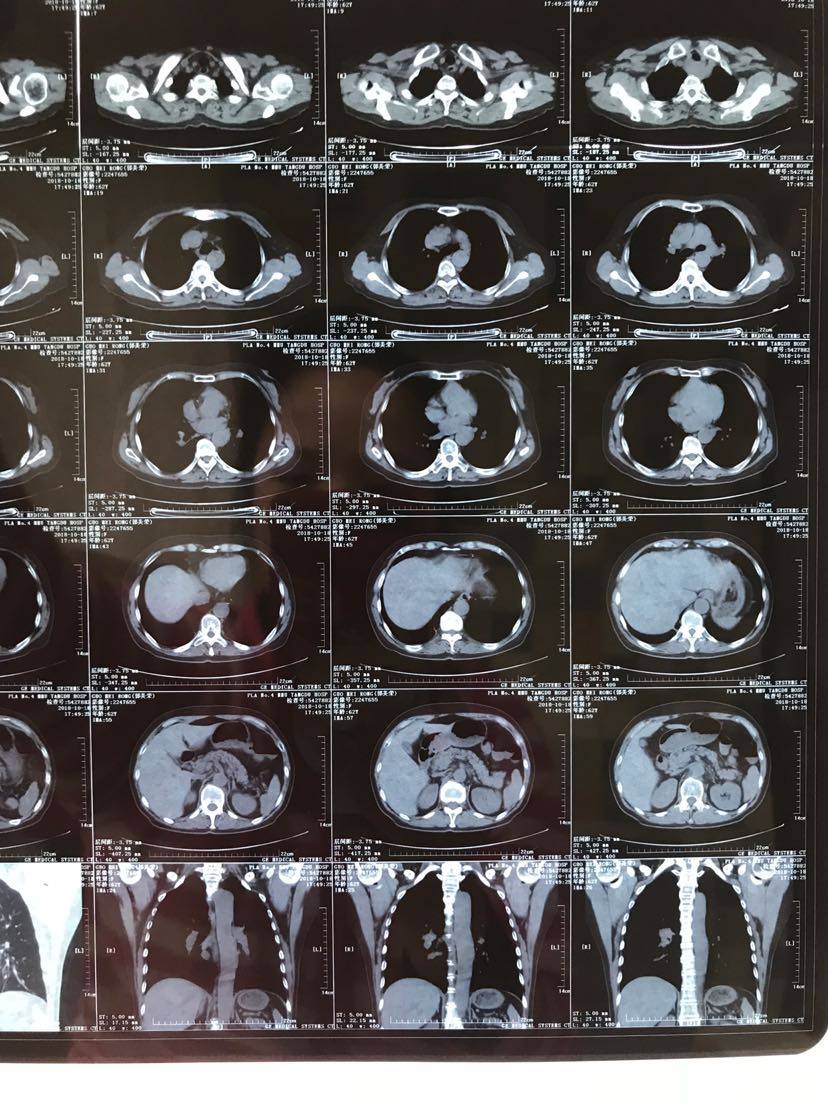

(3)

举报

病历.患者,女,62岁,身高163,体重55公斤。2017年5月确诊肺腺癌晚期,胸膜转移,基因检测19突变,服用特罗凯至今。cea不敏感。近3个月体感变差,胸部牵扯痛,深呼吸痛,ca199从个位数升到74。周五复查发现进展了,如下图。

新增大的结节对特罗凯的反应应该不太敏感的,可以考虑穿插化疗看看